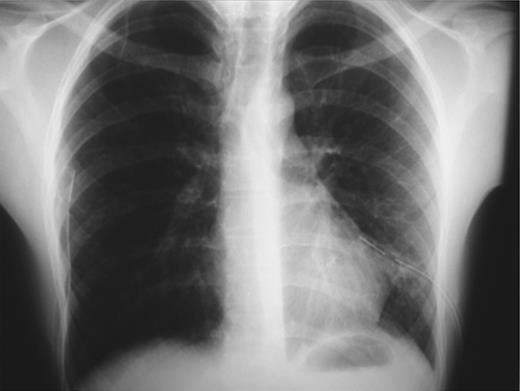

On emergency basis, the patient was managed with bilateral tube thoracostomy through the fifth intercostal spaces. During hospitalization, both lungs were gradually expanded; the use of continuous aspiration was necessary for a couple of days, in order to achieve complete expansion of the left lung (Fig. 2). Both chest tubes were removed on the fifth day of hospitalization. Next day the plain X-ray revealed recurrence of pneumothorax on the left side (Fig. 3). A chest tube was reinserted. Continuous suction was used and complete expansion of the left lung was succeeded. The tube was removed after 5 days; no recurrence took place at this time. During the next 3 days the patient remained under observation; serial physical examinations and chest X-rays were normal and the patient was discharged home.

Recurrence of pneumothorax on the left side after removing the chest tube.